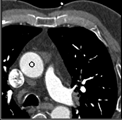

Samples for ascending aorta detection (black circle):

Cluster of candidate points in the ascending aorta.